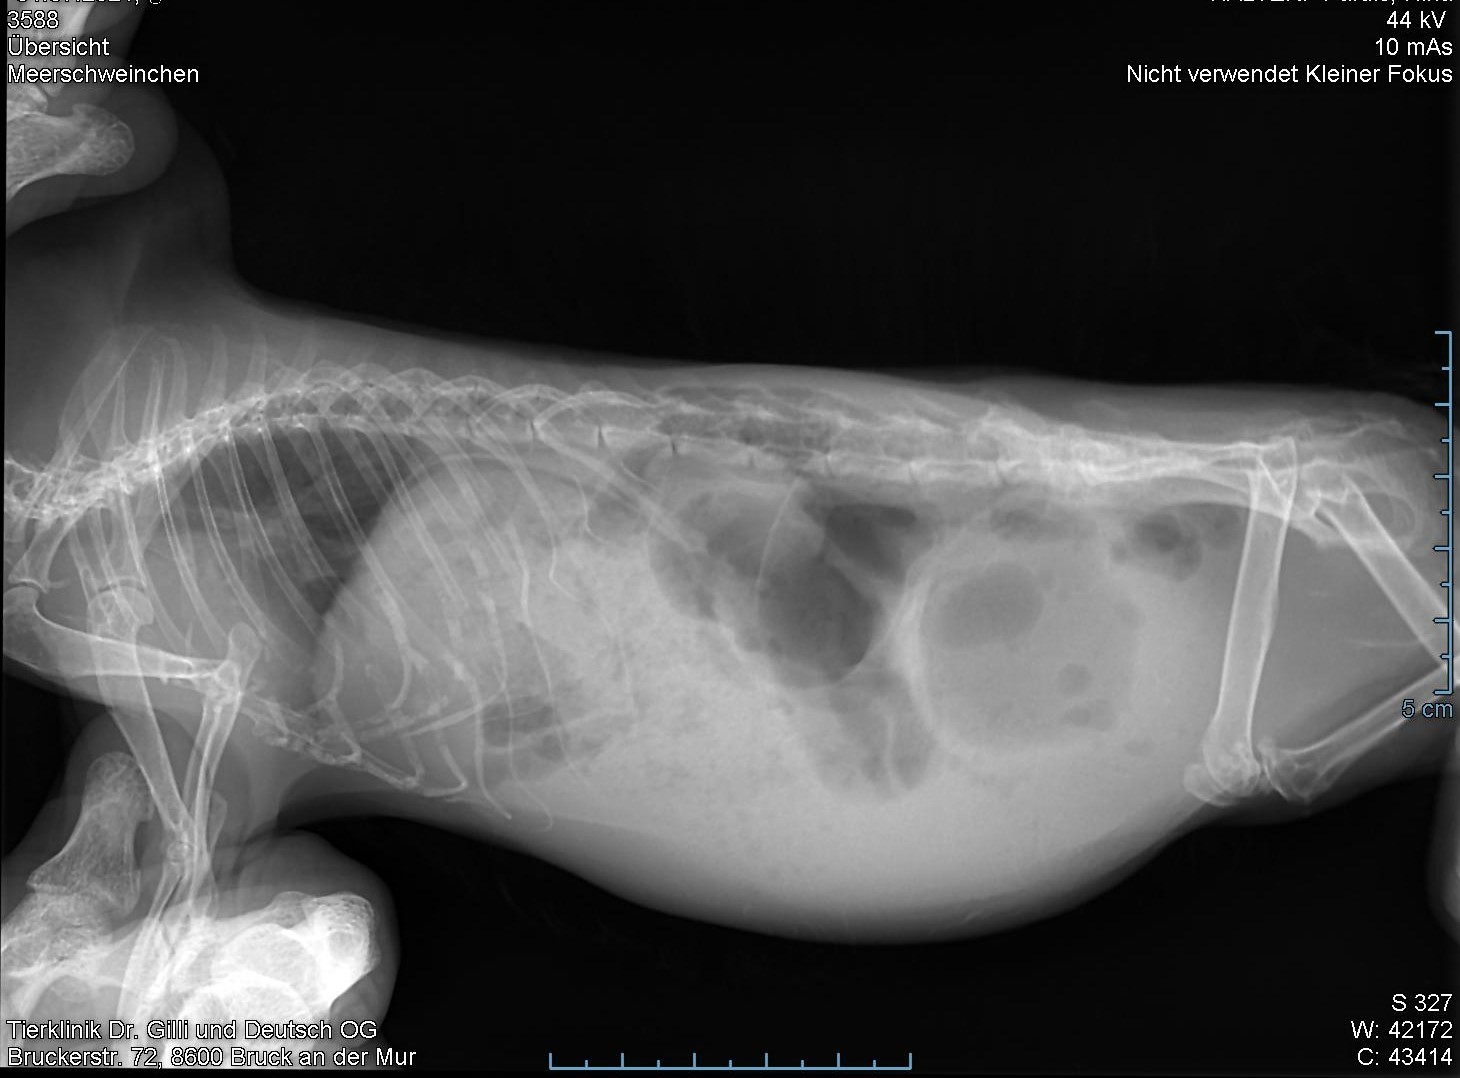

Es ist daher wichtig umfassende Diagnostik zu machen. Ein Ganzkörperröntgen in zwei Ebenen ist immer gut und wichtig. Daraus ergeben sich oft weitere Behandlungsansätze. Außerdem sollten die Zähne zumindest oberflächlich angesehen werden (sichere Aussagen können nur in einem CT oder Röntgen in Narkose getroffen werden) und Kot eingeschickt werden, wenn sich sonst nichts ergibt. Andere Überlegungen können eine Urinuntersuchung, ein Ultraschall oder ein Blutbild sein. Kommt drauf an, was man im Verdacht hat.

Ich werde sie morgen nach einer Ultraschallunteruchung, einem Röntgen bitte, wenn es der Kleine verkraftet.

Die bisherigen Röntgenaufnahmen würden, wenn Du sie mitnehmen kannst, vielleicht schon reichen. Ansonsten würden sie ein Vergleich über die letztenTage ermöglichen, also ob eine Besserung eingetreten ist. Man muss halt immer bedenken, dass für Meerschweinchen Röntgen, Ultraschall, Blutabnahme und Zähneuntersuchen eine Belastung sind. Alles zusammen würde ich ihm nicht zumuten, solange er noch nicht wieder stabil ist bzw. es wirklich nötig erscheint.

Da er das erste Mal mit so etwas zu kämpfen hatte, möchte sie ihm die einzelnen Untersuchungen noch nicht antun und auch auf den Stress eines erneuten Röntgen wollte sie verzichten.Falls es wieder vorkommt werden wir meine Protokolle auswerten und Röntgen, Ultraschall, Blutabnahme und Zähneuntersuchen durchführen, um die Ursache festzustellen.

Anbei noch das Röntgenbild.